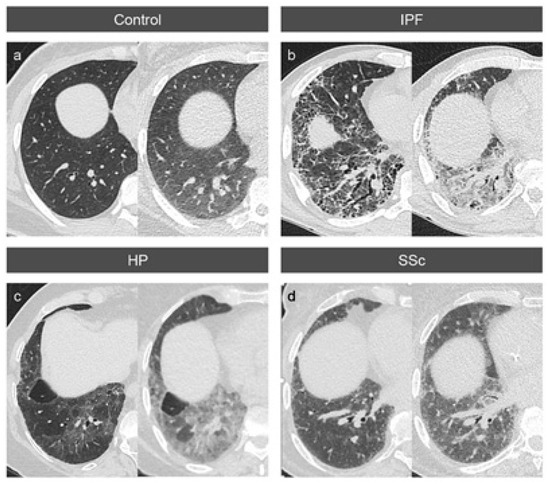

2.2. Thorax CT and Imaging Modalities

3.2. Absolute Attenuation Values

3.3. Attenuation Differences between Inspiration and Expiration

3.4. Variable Density Increases in the Lung Lobes